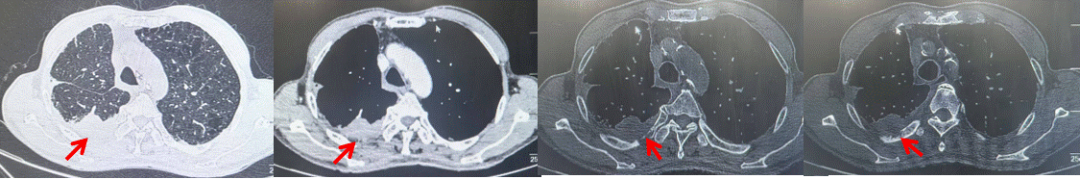

2024.09.12复查胸部CT示左侧胸膜结节,大者约为27mmx13mm,考虑转移可能性大,纵隔淋巴结增大,恶性?(如图6)。患者行胸膜穿刺活检取病理,结果示(胸膜)结合免疫组化,支持鳞状细胞癌,PD-L1(克隆号28-8)TPS约20%。分期为rT0N2bM1a IVA期,DFS为10个月。2024.09.24起行替雷利珠单抗联合紫杉醇+卡铂方案治疗4周期,复查胸CT评效SD(如图7)。后患者因脑梗塞停止治疗,于综合医院就诊,后未返院复查及治疗。

图7:替雷利珠单抗联合白蛋白紫杉醇+卡铂治疗4周期后(2024.12)胸部CT肺窗及纵隔窗